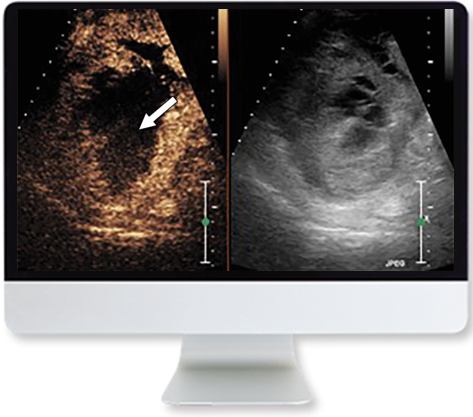

- Contrast Enhanced Ultrasound—Corinne Deurdulian, MD

- Contrast Enhanced Ultrasound-Clinical Applications—Corinne Deurdulian, MD